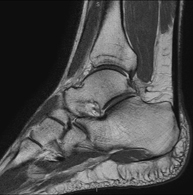

- Ankle MRI

Examination to study the joint and its frequent ligament injuries (sprains) as well as damage to other structures such as cartilage or bone. It is also very useful for diagnosing disorders of the Achilles tendon (tendinitis, ruptures). Duration: approximately 20 minutes. It is a radiation-free procedure.